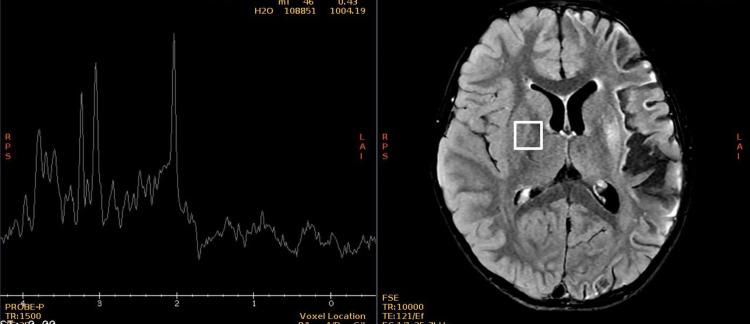

A three-year-old female patient was admitted to our institution due to subacute fever, intermittent vomiting, persistent bilateral mydriasis after cycloplegia, right central facial palsy, and mild right hemiparesis with hyperreflexia. Brain MRI shows encephalitis in frontal, parietal, insular, and left putamen course and loss of cortical volume and white matter of the entire left hemisphere which are features described in Rasmussen's encephalitis (RE). Therapy with intravenous methylprednisolone bolus was initiated, with adequate clinical response. We consider in this case the diagnosis of atypical RE by imaging criteria in the subacute stage. There are few reports of atypical RE without epilepsy or continuous partial epilepsy. Our purpose is to present a case of a patient with RE images without epilepsy seizures and review the diagnostic and therapeutic approach of RE.

摘要

一名三岁女性患者因亚急性发热、间歇性呕吐、睫状肌麻痹后持续性双侧瞳孔散大、右侧中枢性面瘫以及伴有反射亢进的轻度右侧偏瘫入住我院。脑部磁共振成像显示额叶、顶叶、岛叶及左侧壳核部位存在脑炎,且整个左半球皮质体积和白质减少,这些都是拉斯穆森脑炎(RE)所描述的特征。开始采用静脉注射甲泼尼龙冲击治疗,临床反应良好。我们根据亚急性期的影像学标准考虑该病例为非典型RE。关于无癫痫或持续性部分性癫痫的非典型RE报道较少。我们的目的是呈现一例无癫痫发作的RE影像患者病例,并回顾RE的诊断和治疗方法。